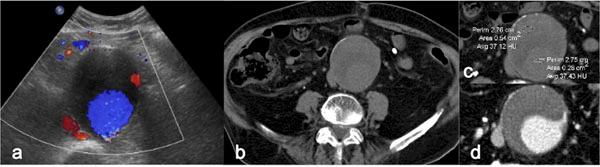

Acute vascular emergencies can arise from direct traumatic injury to the vessel or be spontaneous (non-traumatic).The vascular injuries can also be divided into two categories: arteial injury and venous injury.Most of them are life-treatening emergencies, sice they may cause an important ipovolemic shock or severe ischemia in their end organ and require prompt diagnosis and treatment.In the different clinical scenarios, the correct diagnostic approach to vascular injuries isn't firmly established and advantages of one imaging technique over the other are not obvious.Ultrasound (US) is an easy accessible, safe and non-invasive diagnostic modality but Computed Tomography (CT) with multiphasic imaging study is an accurate modality to evaluate the abdominal vascular injuries therefore can be considered the primary imaging modality in vascular emergencies.The aim of this review article is to illustrate the different imaging options for the diagnosis of abdominal vascular emergencies, including traumatic and non traumatic vessel injuries, focusing of US and CT modalities.

急性血管急症可由血管直接外伤引起,也可为自发性(非外伤性)。血管损伤也可分为两类:动脉损伤和静脉损伤。它们大多是危及生命的急症,因为它们可能导致重要的低血容量性休克或其终末器官的严重缺血,需要及时诊断和治疗。在不同的临床情况下,针对血管损伤的正确诊断方法尚未完全确立,一种成像技术相对于另一种成像技术的优势并不明显。超声(US)是一种易于获得、安全且无创的诊断方式,但多期成像研究的计算机断层扫描(CT)是评估腹部血管损伤的准确方式,因此可被视为血管急症的主要成像方式。本文综述的目的是阐述用于诊断腹部血管急症的不同成像选择,包括外伤性和非外伤性血管损伤,重点介绍超声和CT方式。